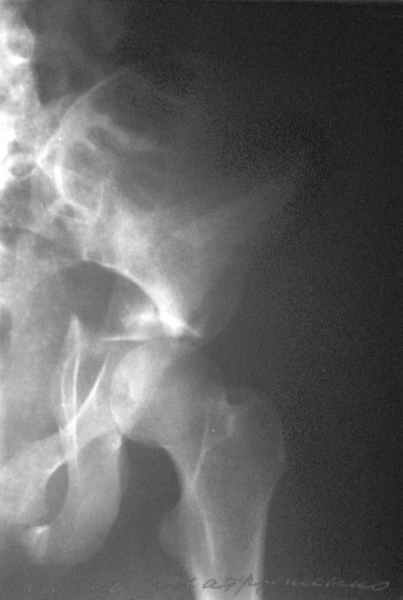

прикладываю схему доступа и случай.